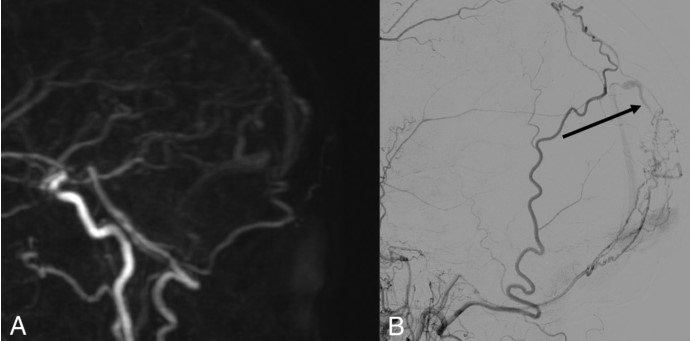

图3. A.动脉晚期4D-MRA矢状位。B.经左侧颈外动脉行脑血管造影矢状面。B中的黑色箭头显示枕静脉早期显影,A中未发现动静脉分流。